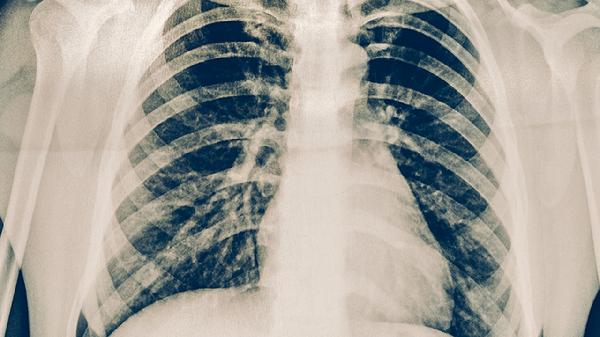

肺结核患者在没有出现明显症状且病情稳定时,一般可以适当进行轻体力活动。如果处于急性发作期或伴有咯血、发热等症状,通常不能干体力活。肺结核是由结核分枝杆菌感染引起的慢性传染病,建议患者在医生指导下调整活动强度。

肺结核急性期患者绝对禁止从事搬运、建筑等重体力劳动。此时肺部存在活动性炎症病灶,剧烈活动可能诱发咯血或气胸。对于合并肺空洞、结核性胸膜炎的患者,即使轻微活动也可能导致呼吸困难加重。这类患者需要严格卧床休息,连如厕等基本活动都需在他人的协助下完成。

肺结核患者恢复期应定期复查胸部CT和痰培养,根据病灶吸收情况逐步增加活动量。日常需保持高蛋白饮食,每日摄入鸡蛋、鱼肉等优质蛋白不少于80克。注意与其他家庭成员分餐,咳嗽时用肘部遮挡口鼻。若出现夜间盗汗或体重持续下降,应及时就医调整治疗方案。